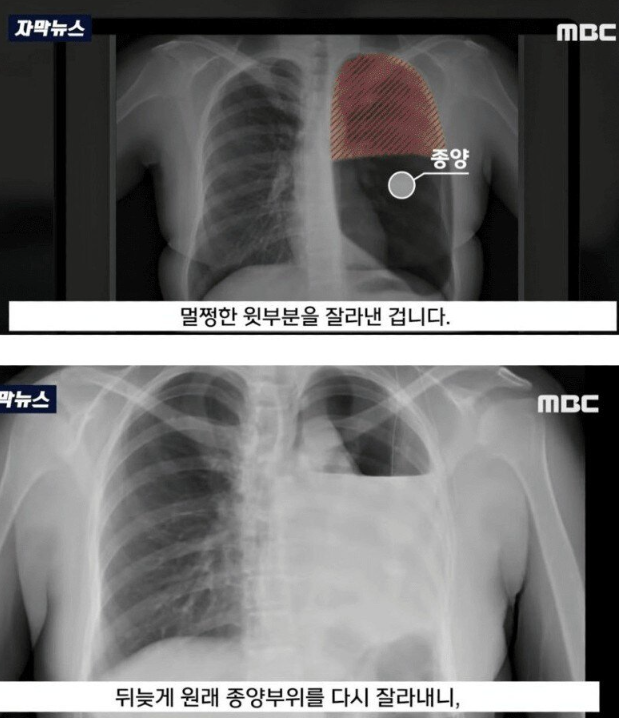

수술이후 알게된 충격적인 진실